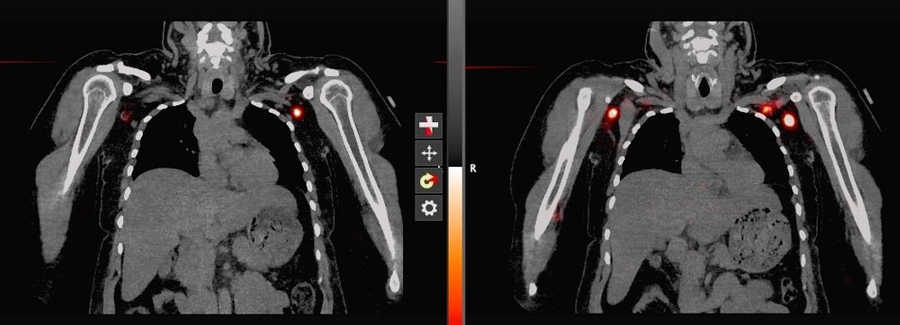

SPECT CT

SPECT/CT Lymphoscintigraphy:  SPECT/CT stands for single-photon-emission computed tomography. This scan consists of combining a CT scan (which lets us see your anatomy clearly) with a scan that tracks the progression of a tracer through that anatomy over a certain period of time. It lets us see the volunteer's anatomy with clarity as the tracer moves through.